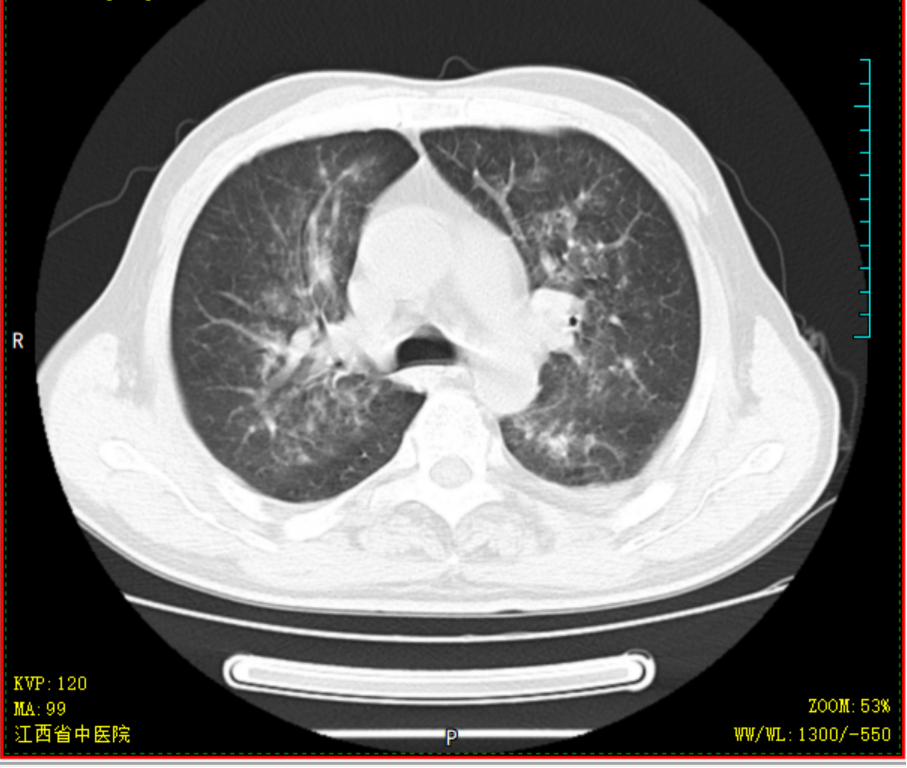

胡大爷,男,69岁,2020-4-14因“头晕乏力”就诊某省级医院,完善骨髓细胞学等检查后诊断为AML-M2a型,中危组;排出化疗禁忌症后,予标准DA方案化疗治疗,化疗过程中出现持续高热,热峰39.5℃,肺部感染、重症肺炎,恶心呕吐明显,予美罗培南+万古霉素抗感染,伏立康唑抗真菌感染,输注红细胞、血小板等治疗,化疗结束后复查骨髓细胞学示AML-NR骨髓象(急性髓系白血病未缓解骨髓象),经40天住院治疗病情平稳后出院,出院时体重减轻10kg。因为恐惧化学治疗,自行停化疗。2020-07-23患者因疲劳乏力加重就诊于金瓶梅电影 ,要求中医调理,入院查血常规示重度贫血、血小板减少,生化示肝功能不全、高尿酸;骨髓提示AML-NR骨髓象(急性髓系白血病未缓解骨髓象)。入院后予中药汤剂益气养血,并热敏灸温通经络。经治疗后患者乏力疲劳、贫血明显改善,排除治疗禁忌后,08-13起减低剂量化学治疗,同时口服我科经验方参芪杀白汤益气养血、扶正祛邪抗肿瘤,同时调理脏腑气机减少化疗不良反应,起增效减毒之功;热敏灸疗法灸肺腧穴固护肺卫之气预防外邪入侵,灸脾腧穴、肾腧穴固先后天之本促进气血化生。全程未出现呕心呕吐、骨髓抑制等常见不良反应,09-07骨髓细胞学示AML-CR骨髓象(急性髓系白血病完全缓解骨髓象)、白血病微小残留MRD提示阴性。2020-09-08返院行中西医结合方案抗白血病治疗,过程顺利,结束治疗后09-15出院 。经西医结合治疗不但是患者的症状改善明显,同时提高患者生活质量,同时保证了患者的临床疗效。